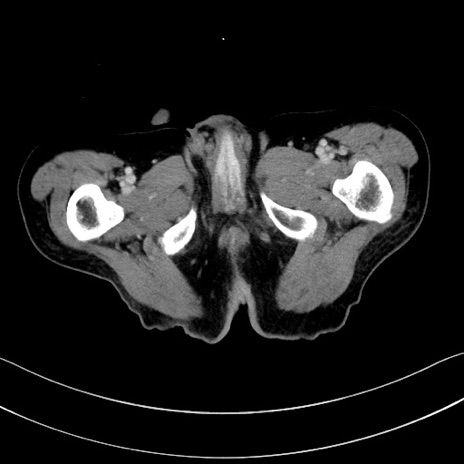

症例28(横断像)

【症例】60歳代男性

【主訴】嘔吐

【現病歴】胃癌にて胃全摘後。食思不振が悪化し、夜中に嘔吐することがある。

【既往歴】胃癌、胃全摘、脾摘、胆摘後

【データ】WBC 5900、CRP 10.56